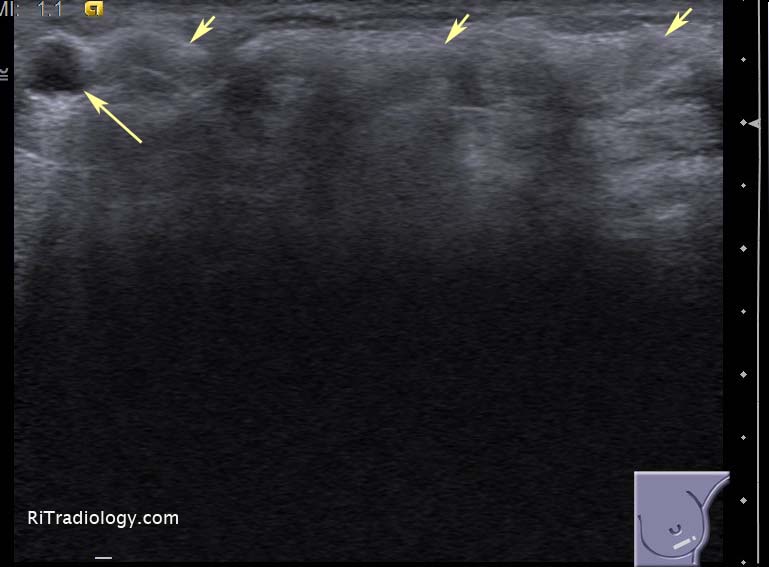

El ultrasonido mamario es una herramienta diagnóstica fundamental para evaluar el tejido mamario y detectar posibles alteraciones. En mujeres jóvenes, esta técnica adquiere particular importancia debido a las características específicas del tejido mamario y a las recomendaciones médicas relacionadas con la prevención y el diagnóstico temprano.

El ultrasonido mamario es una herramienta diagnóstica clave para evaluar el tejido mamario y detectar posibles alteraciones, desde lesiones benignas hasta cáncer. En los últimos años, la tecnología ha avanzado y ha permitido el desarrollo de ultrasonidos en 3D, que ofrecen imágenes tridimensionales del tejido mamario. Esto ha generado interés sobre si el ultrasonido mamario en 3D es superior al ultrasonido convencional y en qué casos se recomienda uno u otro.